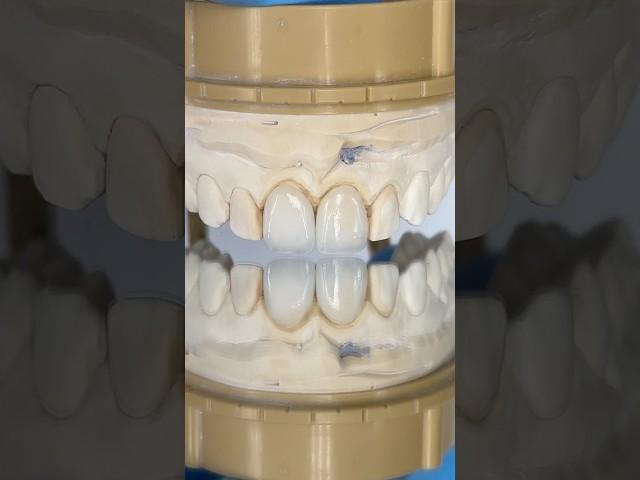

Central Veneer Incisors #lsk121shorts #dentist #teeth